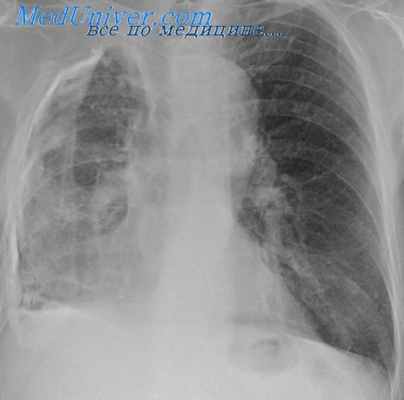

Диагностика травматического пневмоторакса

Рентгенография грудной клетки

Обычно диагноз устанавливают с использованием рентгенографии. Ультрасонография (выполняется у постели больного во время начальной реанимации, расширенная целенаправленная оценка с помощью сонографии при травме (Extended Focused Assessment With Sonography in Trauma)[E-FAST]) и КТ более чувствительны при небольшем пневмотораксе, чем рентгенография грудной клетки.

Размер пневмоторакса, выраженный в процентах от объема гемиторакса, занятого воздухом, может быть оценен на основании результатов рентгенографического исследования Диагностика Пневмоторакс – это скопление воздуха в плевральной полости, что приводит к частичному или полному коллапсу легкого. Пневмоторакс может развиваться спонтанно, в результате травм или медицинских. Прочитайте дополнительные сведенияЛечение травматического пневмоторакса